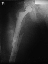

Произведено закрытое удлинение ножки эндопротеза с помощью ретроградного интрамедуллярного стержня. Продолжительность операции 3 часа. Два из них закрытое восстановление длины бедра диистрактором

таз-бедро.

новые снимки